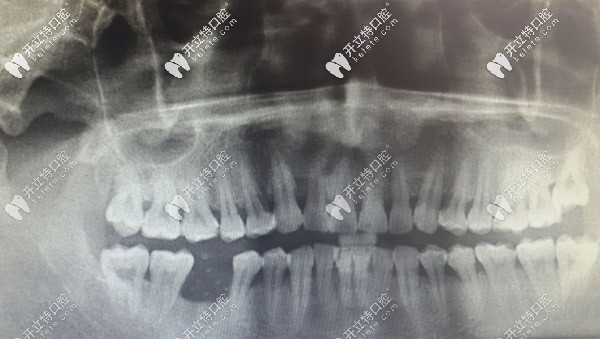

從顧客的曲斷X線片,可以看到右下6的牙槽骨明顯低于相鄰牙齒,已經(jīng)吸收,出現(xiàn)三度松動。右下6也出現(xiàn)了二度松動,勉強保留一定的要和功能。

半個月后來復診,查看牙窩有膿液溢出,且腫脹沒有消退,決定拍片看。片子顯示右下5有陰影,且陰影有一高密度區(qū),診斷有死骨形成,局麻取出死骨。

之后有來復診,右下5區(qū)還是腫脹有膿溢出。拍了曲斷牙片后顯示無異常,針對此情況,拍CBCT片顯示右下4根尖有少許陰影,其他都是陰性。